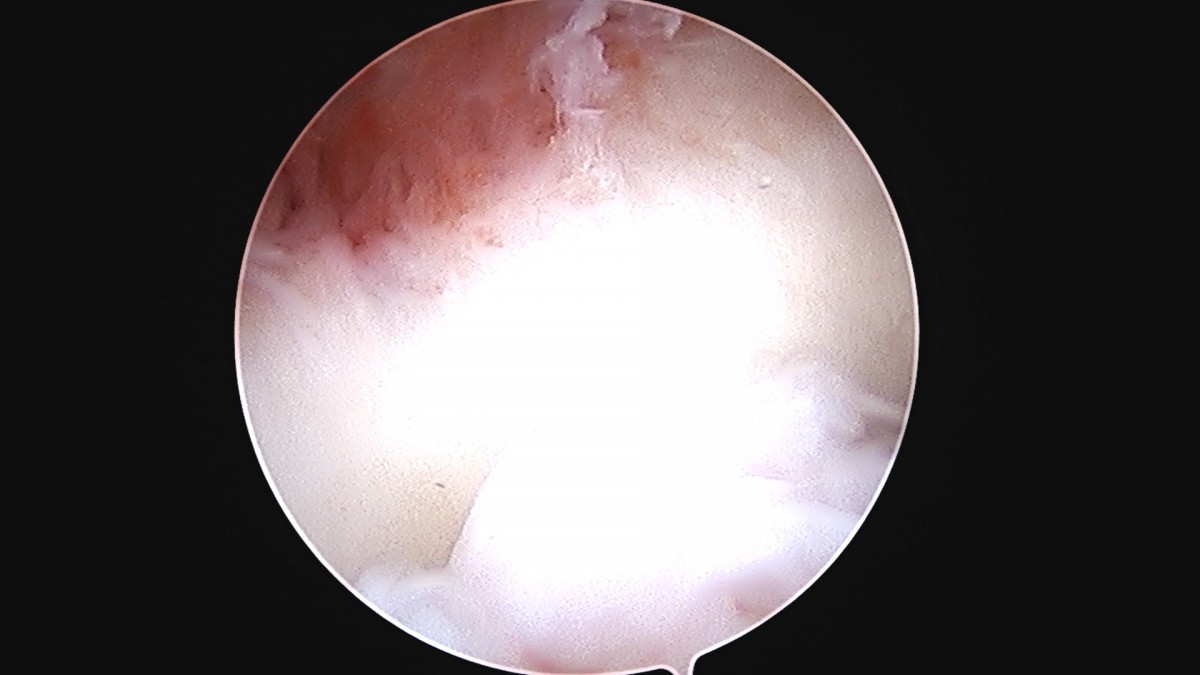

정지영원장님 손목 삼각섬유연골 복합체 봉합술 박현O 환자

작성자 최고관리자 댓글 0건 조회 778회 작성일 25-09-16 16:50